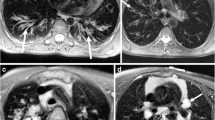

All patients with CPFE were subjectively correctly identified on LGE-MRI. Figures 2 and 3 provide imaging examples in two patients with CPFE of LGE in regions of pulmonary fibrosis in the lower lobes and an absence of LGE in regions of emphysema in the upper lobes. The contrast-to-noise ratio was 30.1. Table 2 shows the median SI in regions of fibrosis and emphysema. Qualitatively, emphysema showed no evidence of LGE-MRI enhancement in any patient. Quantitatively, significant differences were found in median SI in regions of fibrosis compared to regions of emphysema (25.8, IQR 18.4–31.0 versus 5.3, IQR 5.0–8.1, p < 0.001). ROC analysis of SI in fibrotic areas in the lower lobes compared to emphysematous areas in the upper lobes in CPFE patients showed an area under the curve of 0.95, p < 0.0001. Using a SI value of ≥ 12 resulted in a sensitivity of 95% and specificity of 100% in differentiating fibrosis from emphysema in CPFE patients (Fig. 4). The percentage of SI increase in pulmonary fibrosis compared to emphysema was 278.5% while the percentage of density increase in pulmonary fibrosis compared to emphysema on HRCT was 36.4%. Significant differences were seen between LGE-MRI and HRCT in the extent of reticulation (12.5, IQR 5.0–20.0 versus 15.0–26.3, IQR 5–40, p = 0.038) and honeycombing (5.0, IQR 0.0–10.0 versus 20.0, IQR 10.6–20.0, p = 0.001) but not in traction bronchiectasis (10.0, IQR 5–15 versus 15.0, IQR 5.0–15, p = 0.878 (Table 3).

Seventy-two-year-old woman with progressive breathlessness, FEV1 2.4 L/s, LAV 1.5%. a Axial high-resolution computed tomography showed mild centrilobular emphysema in the upper lobes (arrows). b It was unclear at multidisciplinary conference whether the abnormal regions in the lower lobes (arrows) represented emphysema or fibrosis. c Late gadolinium-enhanced magnetic resonance imaging of the upper lobes showed no contrast enhancement, but in d, definite contrast enhancement was observed in the abnormal regions in the lower lobes (arrows) and was consistent with fibrosis. FEV1, Forced expiratory volume in one second; LAV%, Low attenuation value percent

Fifty-seven-year-old man with progressive breathlessness, FEV1 2.4 L/s, LAV 7.6%. a Axial high-resolution computed tomography showed moderate centrilobular emphysema in the upper lobes (arrows). b It was unclear at multidisciplinary conference whether the abnormal regions in the lower lobes (arrows) represented emphysema or fibrosis. c Late gadolinium-enhanced magnetic resonance imaging of the upper lobes showed no contrast enhancement, but in d, definite contrast enhancement in the abnormal regions in the lower lobes (arrows) was consistent with fibrosis. FEV1, Forced expiratory volume in one second; LAV%, Low attenuation value percent